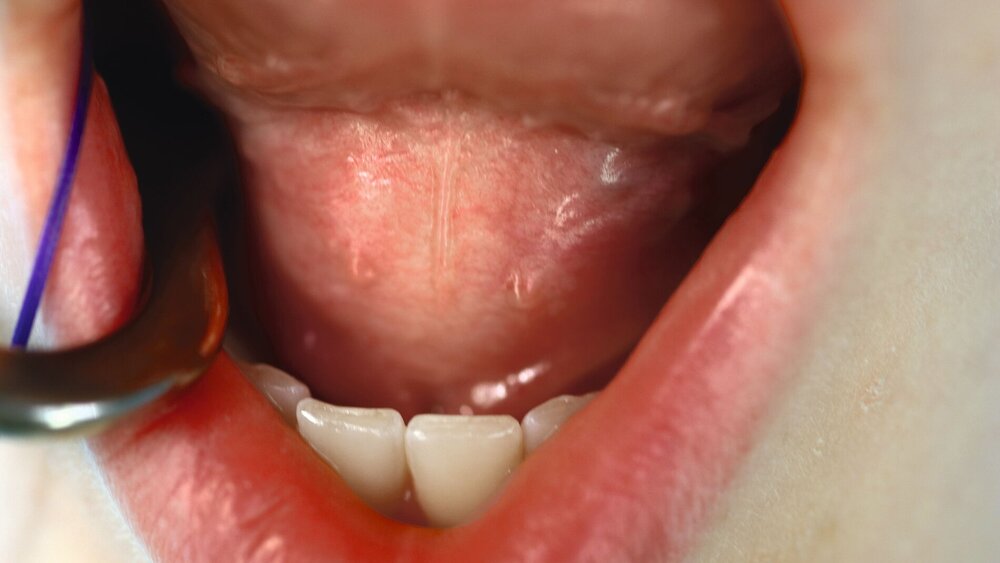

Klinisch zeigte sich eine rundliche Erhabenheit sublingual, die den gesamten Mundboden ausfüllte. Die Palpation ergab eine weiche, nicht druckdolente Raumforderung. Alle Zähne waren vital; ein dentaler Fokus konnte ausgeschlossen werden. Die bereits vorliegende Röntgendiagnostik mittels Orthopantomografie (OPT) (Abbildung 1) zeigte keinen pathologischen Befund. Eine extraorale Schwellung konnte zu diesem Zeitpunkt nicht festgestellt werden.